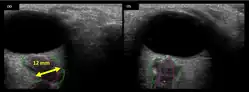

Figure 6: On-orbit ultrasound of optic nerves of the fourth case of visual changes from long-duration spaceflight. In-flight ultrasound shows proximal kinking and increased optic nerve sheath diameter (ONSD) of approximately 12 mm that is consistent with raised ICPs. Optic nerve shown in purple and the ONSD in green.